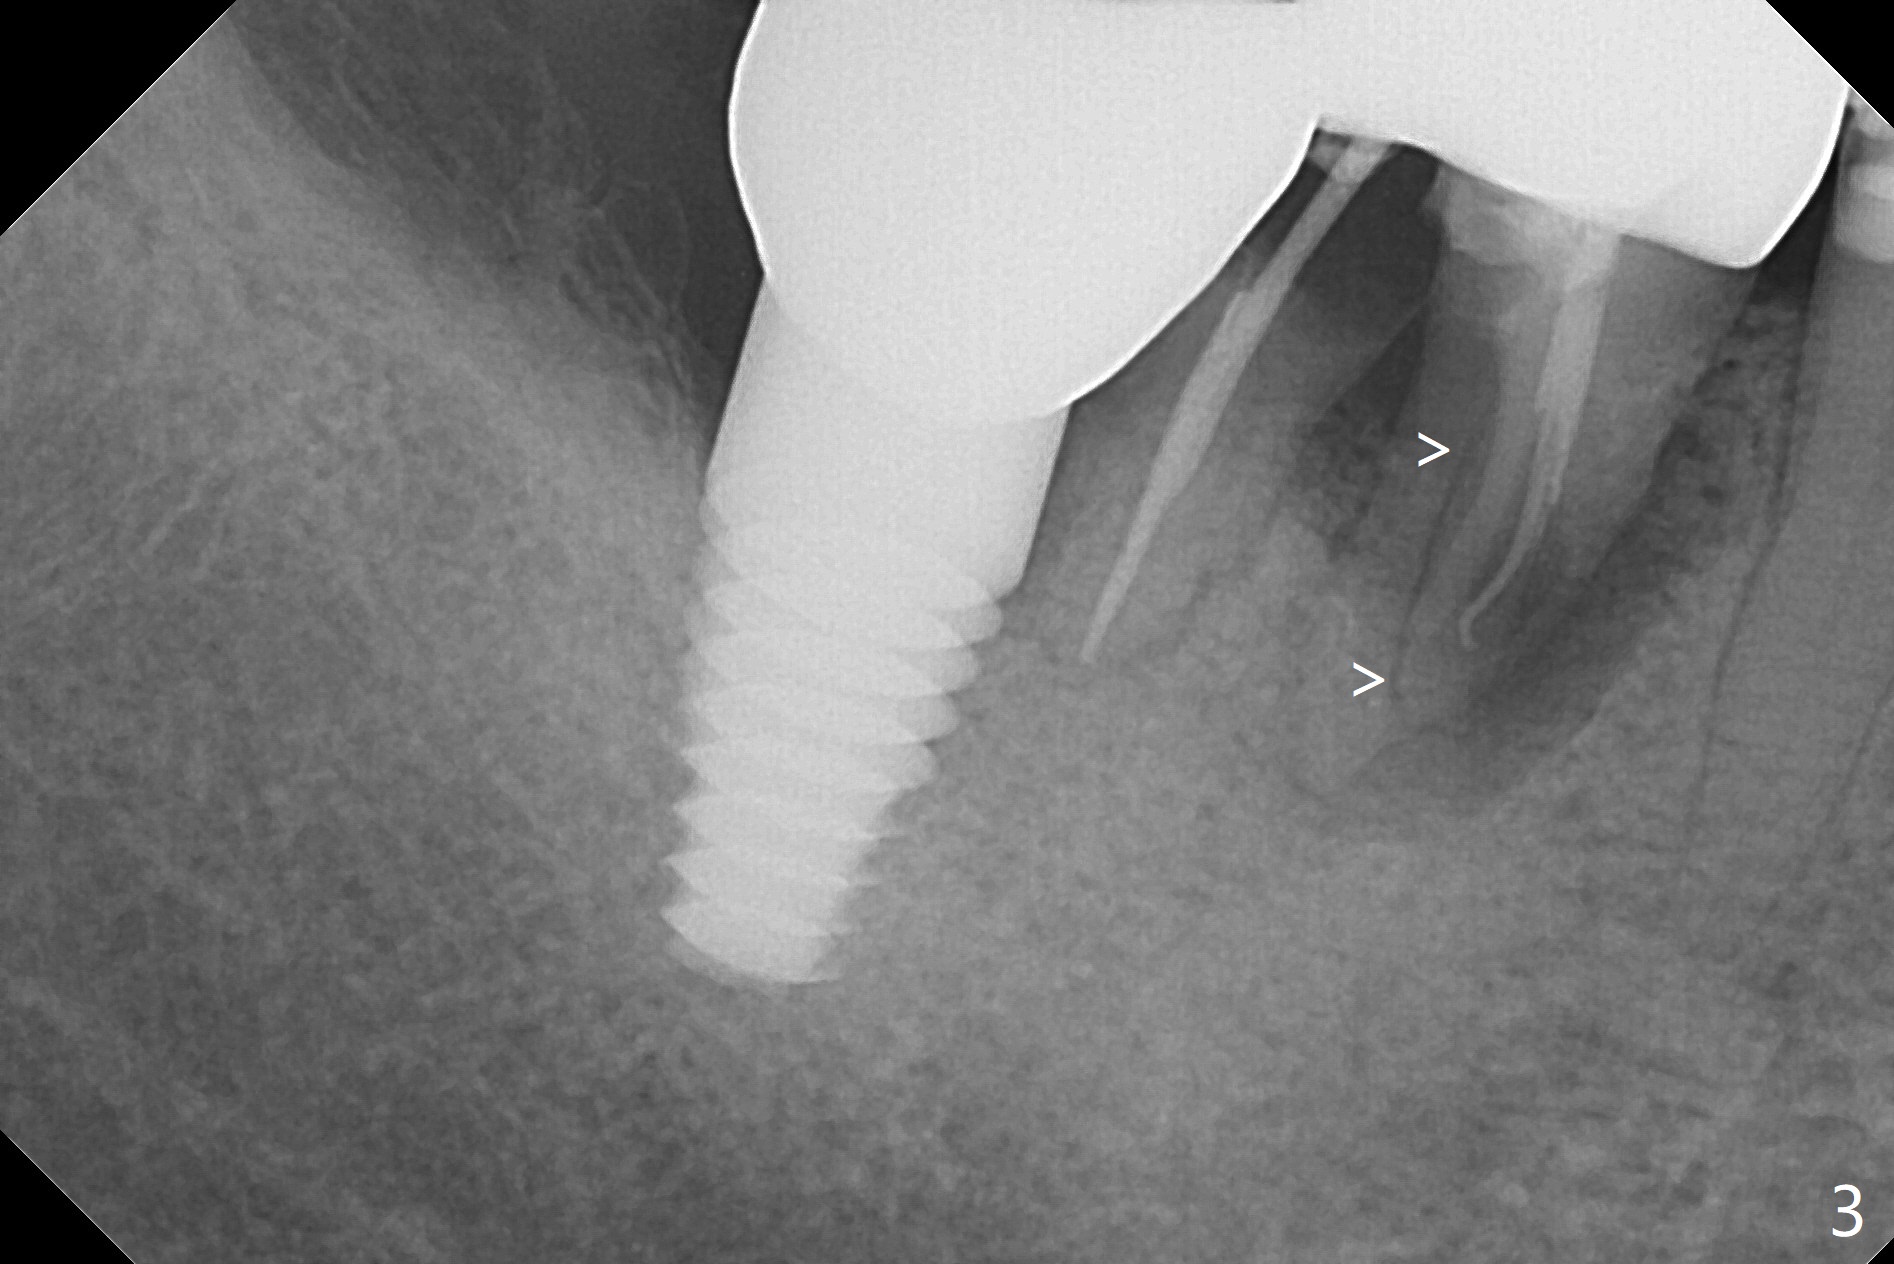

A 67-year-old woman masticates on the right side (Fig.1 (5 years post #30 RCT), as compared to Fig.4,6). One year and 6 months later, there is a fistula mesiobuccal to the tooth #30 (Fig.2 >,4) with mesial root fracture (Fig.3 >). Impression is taken for guide; a 5x11.5 mm implant will be placed slightly distal and lingual to the center of the septum (Fig.5).